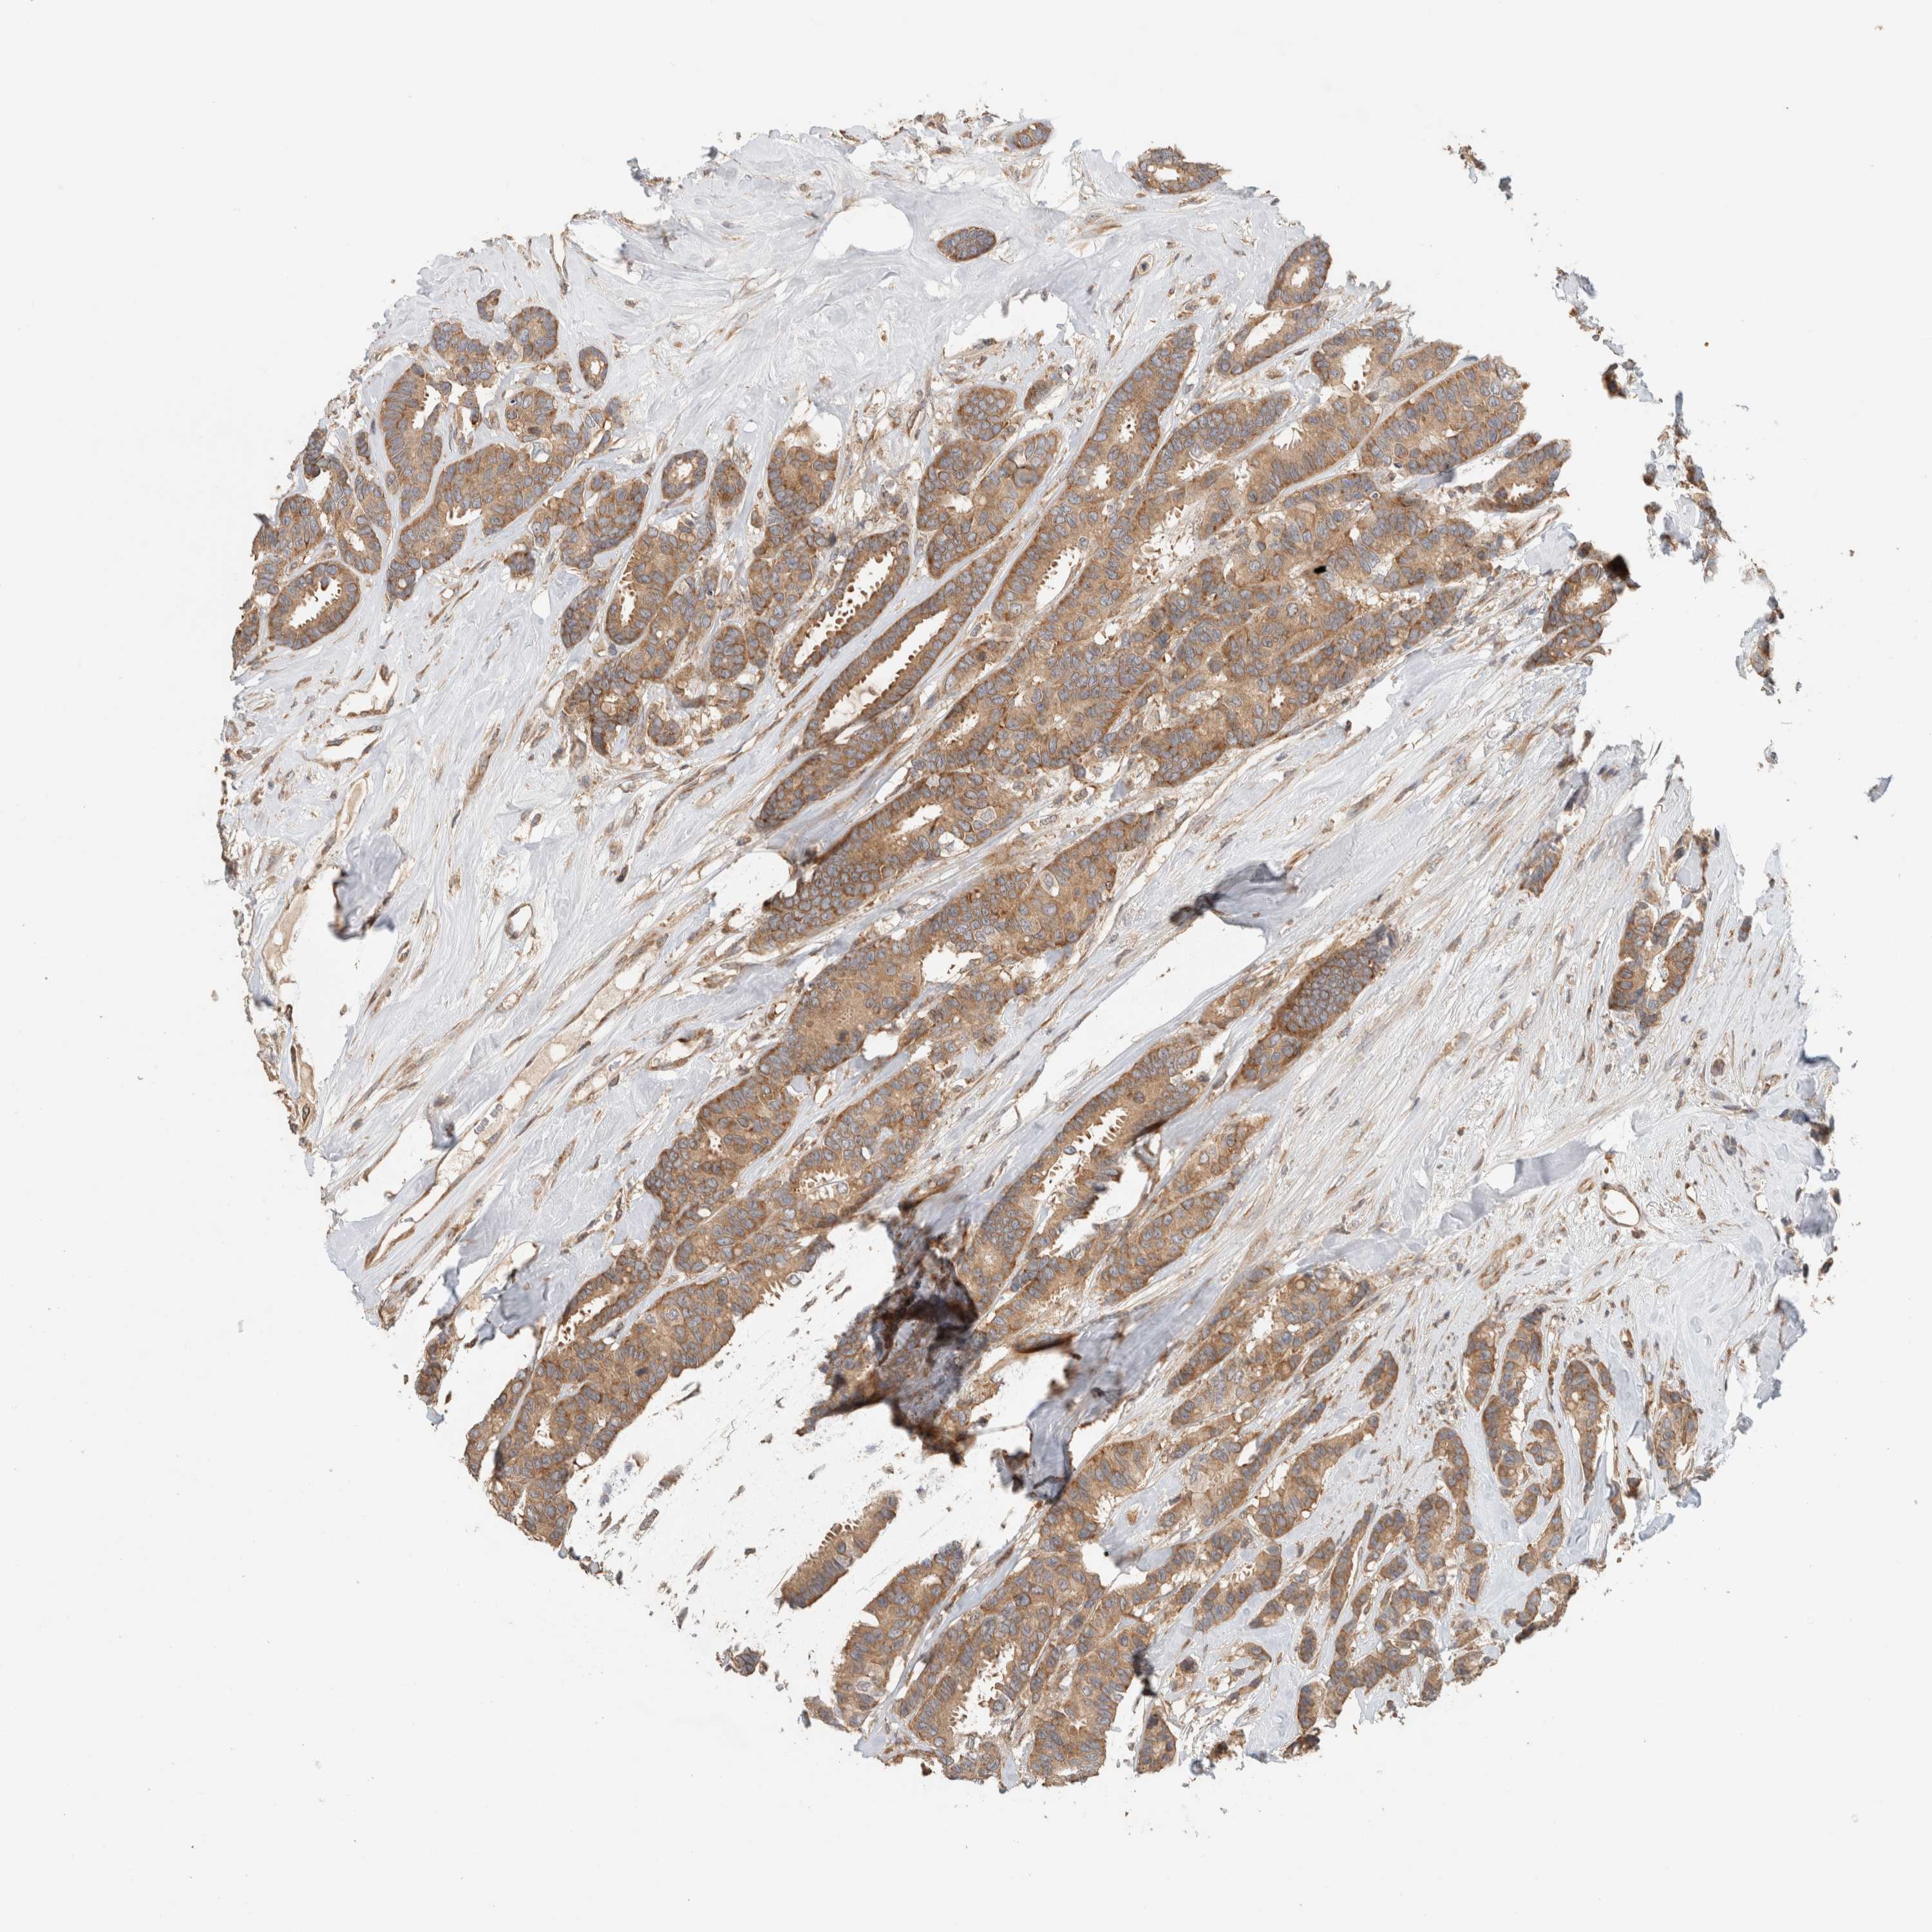

BRCA TCGA BRCA VALIDATION PROTEIN EXPRESSION